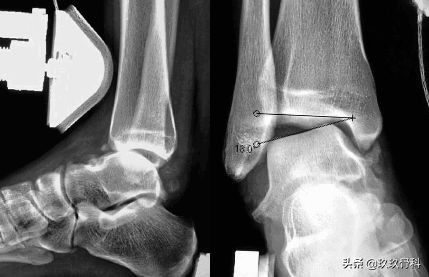

辅助检查

- X线 踝关节正侧位(必要时应加照踝穴位)

应力位片

诊断:体检—疼痛肿胀压痛的部位在踝的前上方;X线—踝内旋20°正位